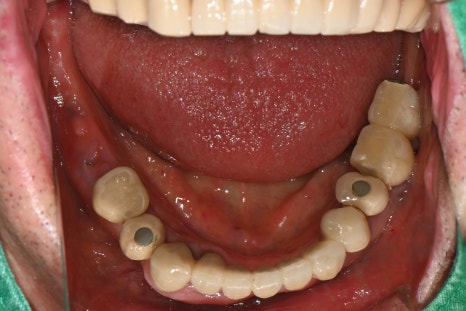

오른쪽 사진: 아랫니는 빠진 크라운과 부러진 임플란트가 있어 전반적인 재정비가 필요했습니다.

오른쪽 사진: 발치한 자리에 식립한 임플란트에 최종 보철이 정확히 체결된 모습입니다.